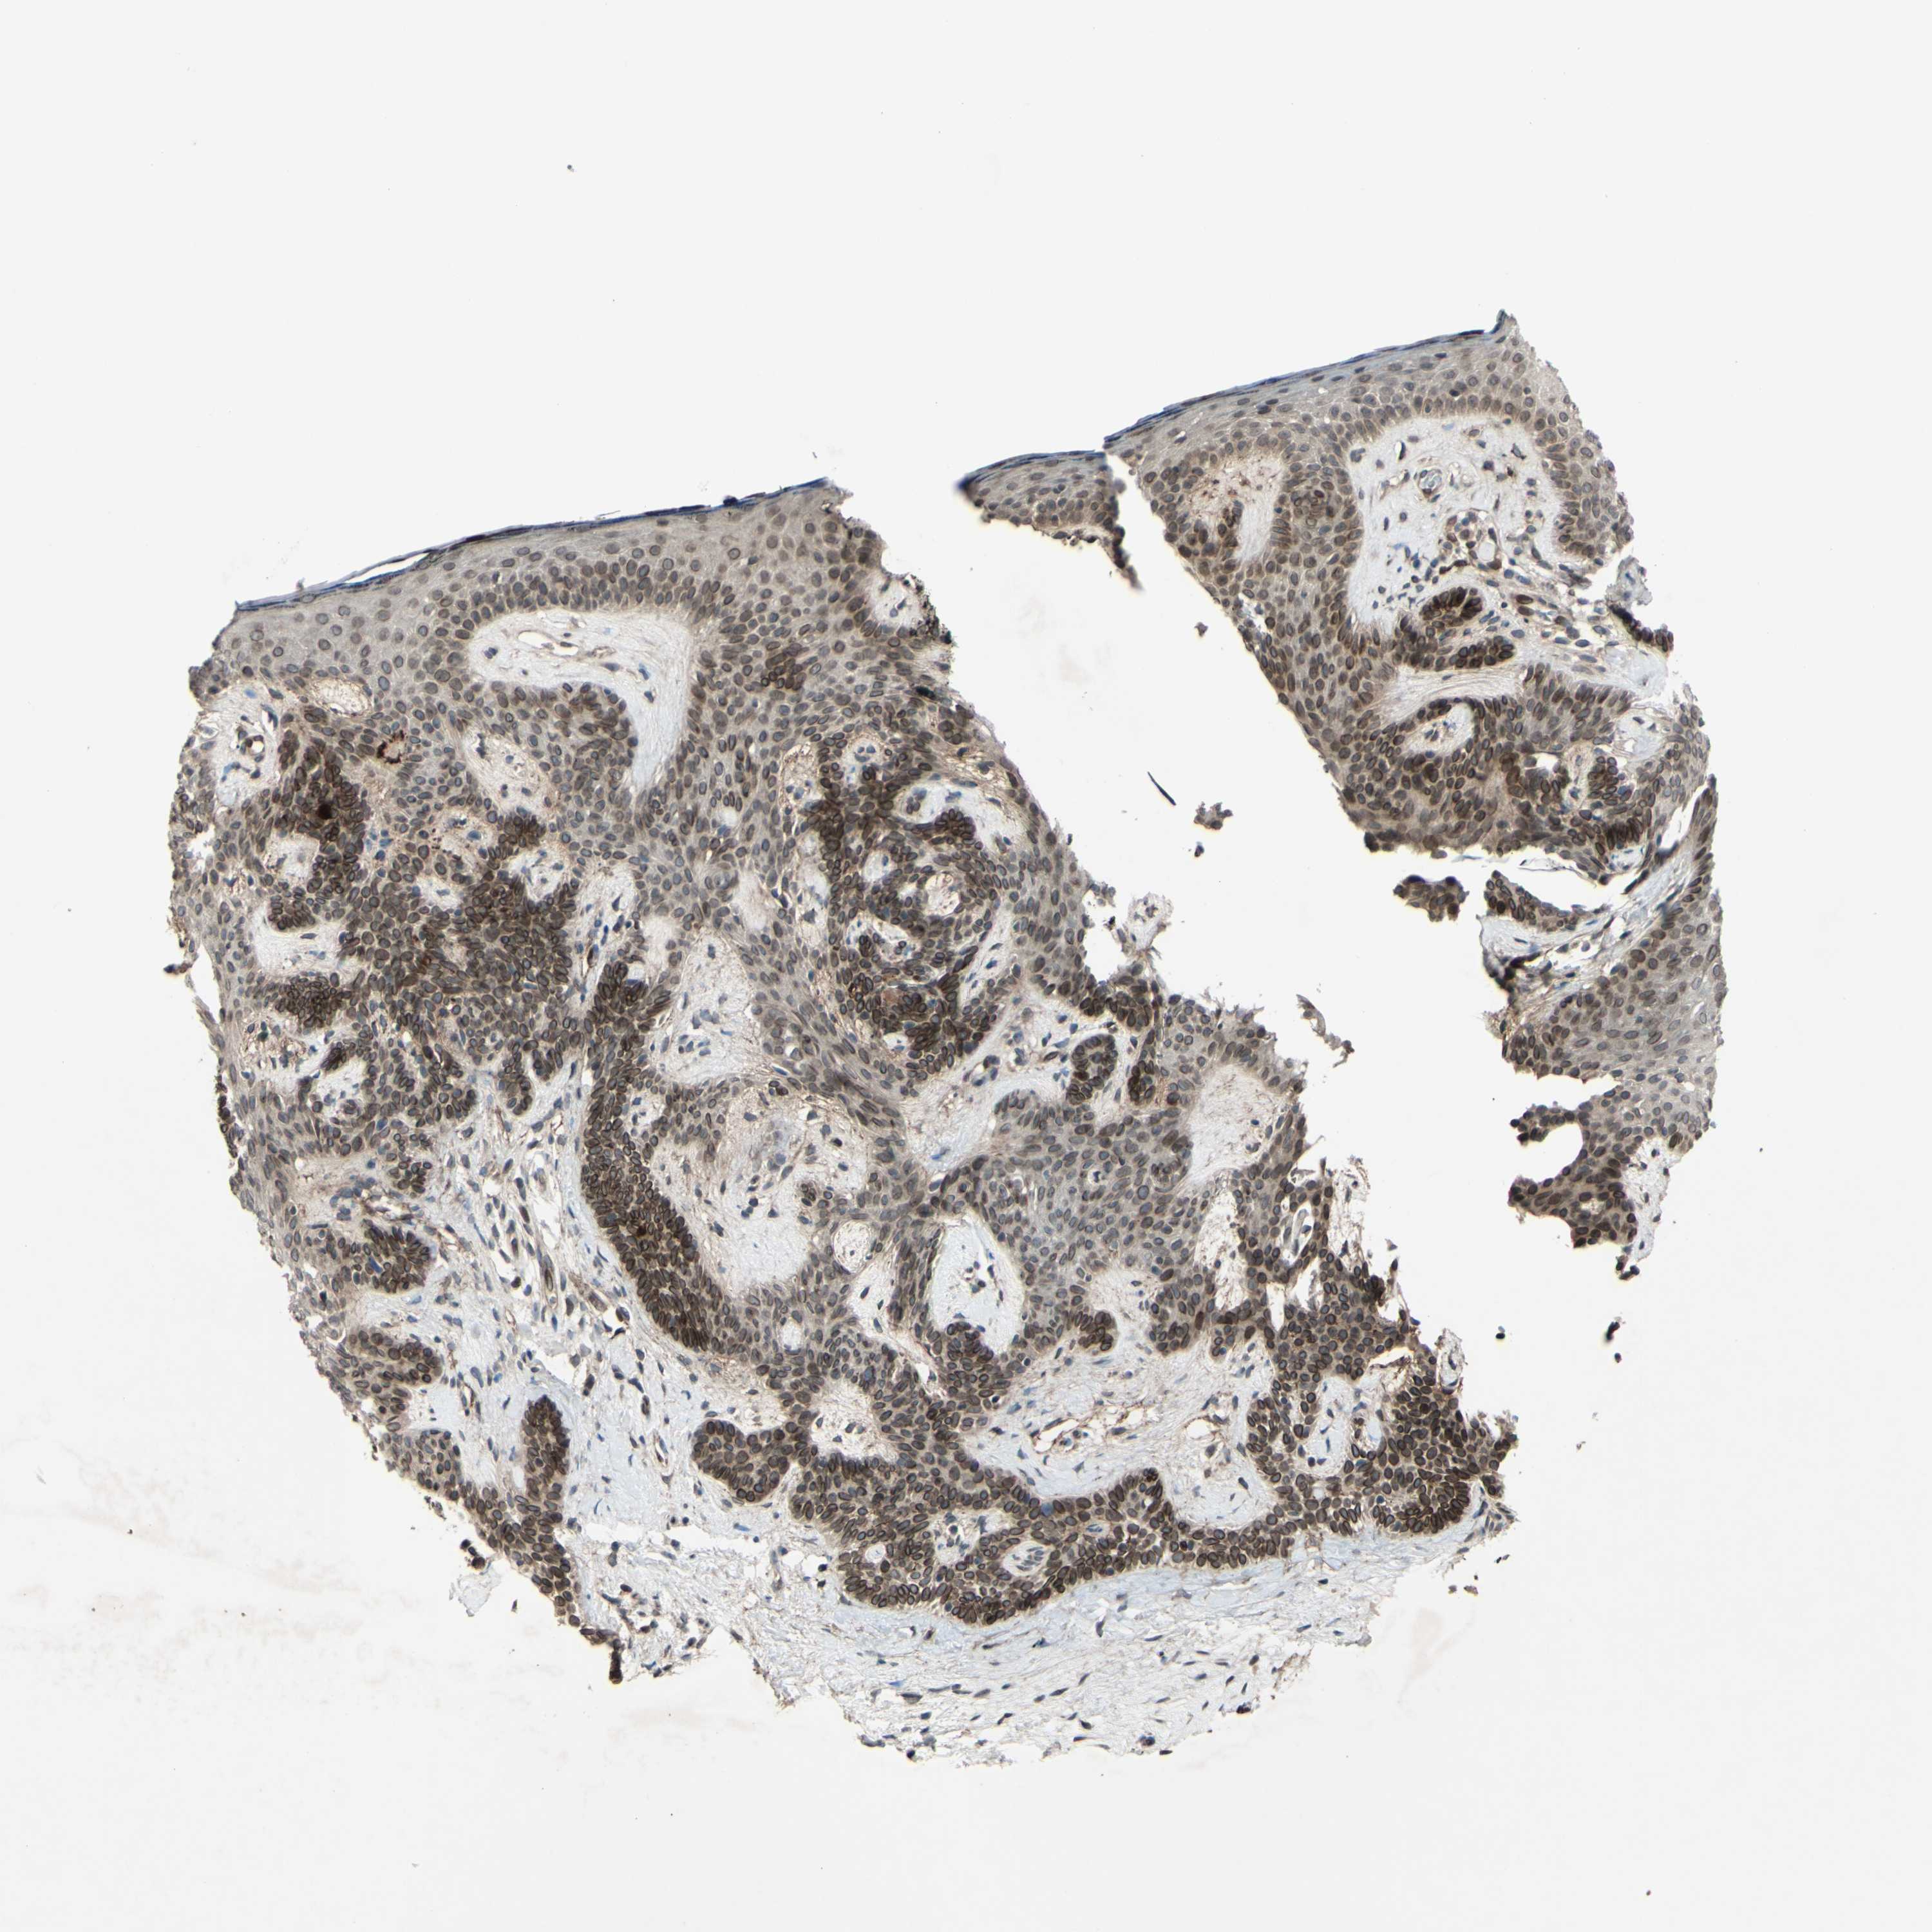

SKIN CANCER - Protein expressioni

A mouse-over function shows sample information and annotation data. Click on an image to view it in a full screen mode. Samples can be filtered based on level of antibody staining by selecting one or several of the following categories: high, medium, low and not detected. The assay and annotation is described here.

Antibody stainingi

Antibody staining in the annotated cell types in the current human tissue is reported as not detected, low, medium, or high, based on conventional immunohistochemistry profiling in selected tissues. This score is based on the combination of the staining intensity and fraction of stained cells.

Each image is clickable and will lead to virtual microscopy that enables deeper exploration of all samples and also displays staining intensity scores, fraction scores and subcellular localization as well as patient and tissue information for each sample.

Antibody HPA010811

Staining

High

Intensity

Strong

Quantity

>75%

Location

Nuclear

Squamous cell carcinoma, NOS